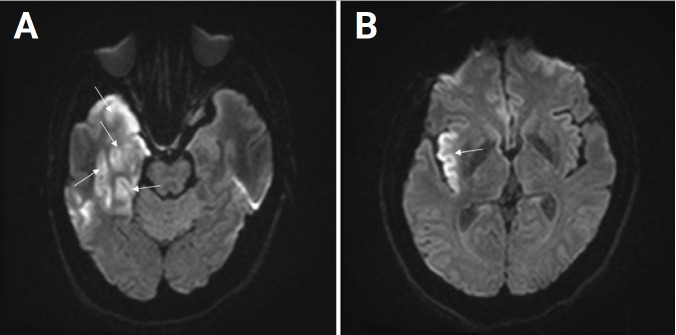

Herpes simplex encephalitis (HSE) is a common viral encephalitis that can be fatal if not adequately treated. Fever, cerebrospinal fluid (CSF) pleocytosis, and typical neuroimaging findings are commonly observed in HSE cases. We encountered a patient with HSE who did not exhibit these classic clinical features. A 63-year-old male presented with his first-ever seizure. Fever did not develop until the fourth day of admission, and neither neuroimaging nor CSF analysis revealed abnormalities. Under suspicion of autoimmune encephalitis, methylprednisolone was administered. Subsequently, when the patient developed fever, a follow-up neuroimaging study was performed and revealed abnormalities consistent with HSE. The patient was promptly treated with acyclovir, which led to a full recovery. Diagnosing HSE in patients who present without fever or CSF pleocytosis and with typical neuroimaging findings poses a challenge. Therefore, prior to initiating immunosuppressive treatment, it is crucial to closely observe patients and to conduct follow-up tests, including neuroimaging and CSF analysis.